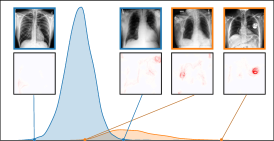

In this section, we leverage latent bias representations, either via directions or individual neurons, to retrieve biased samples and measure how well bias samples are separated from clean samples. We compute bias scores as defined in Eq. 1 by projecting latent activations onto the bias direction. As we are mostly interested in the ranking capabilities, i.e., artifact samples should be assigned higher bias scores than clean samples, we measure Area Under the Receiver Operating Curve (AUROC) and Average Precision (AP), considering both real and controlled artifacts. For real artifacts, we evaluate retrieval using existing artifact labels, while we have ground truth information for controlled experiments. We train CAVs using Support Vector Machines (SVMs) on different layers of VGG16 and ResNet50 models for all datasets, reporting AUROC and AP on unseen test samples. Note, that while Pahde et al. [58] claim that classifier-based CAV computation can yield imprecise concept directions, they argue that SVM-CAVs are superior for predicting concept presence, the main goal of this experiment. In Fig. 7, we show the results for different layers of VGG16 and ResNet50 using single neurons (dashed line) and CAVs (solid line) as bias representation. Best neurons are selected using the validation set. The results indicate that CAVs generally outperform single neuron representations for sample retrieval, and the layer choice is crucial depending on the bias type. For instance, while CAVs for layers closer to the model heads can detect pacemaker samples, they fail for earlier layers.

6.4 Spatial Bias Localization

To spatially localize biases in input space with CAVs, we compute local explanations for the element-wise product of latent activations and concept direction (see Eq. 2). We use the controlled artifacts, specifically timestamp (HyperKvasir) and micropscope (ISIC2019) with ground truth concept localization masks for evaluation. We compute (1) the percentage of relevance within the ground truth mask and (2) the Jaccard index, or Intersection over Union (IoU), of the binarized localization mask with the ground truth. In Fig. 9, we report both metrics using CAVs computed on different layers of VGG16 and ResNet50. The layer choice for concept representations is key, as for example middle layers perform better to localize timestamps and earlier layers are more effective to localize the microscope. In comparison with Fig.7, we find that the optimal layer for bias localization may differ from the one for sample retrieval. Interestingly, the IoU for the microscope artifact is consistently low, as models primarily focus on the border of the circle instead of the entire area, as indicated by qualitative results in Appendix A.6.3. Unlike artifact relevance, the IoU metric also measures how much of the expected areas the computed mask does not cover.